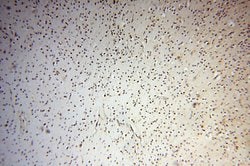

| Immunohistochemistry (Paraffin) | |

| Human, Mouse, Rat | |